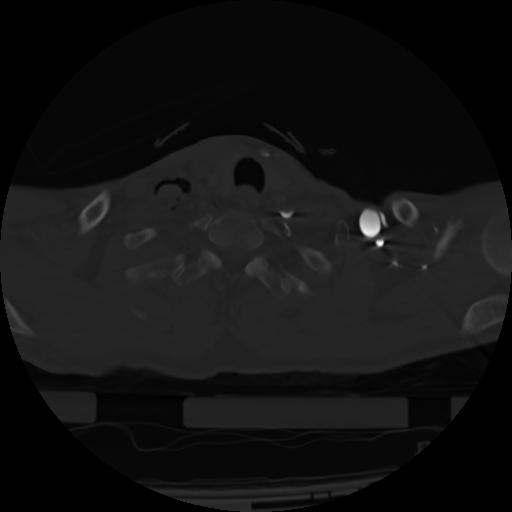

21 ANGIO,CE,Axial,3.0,ANGIO,,